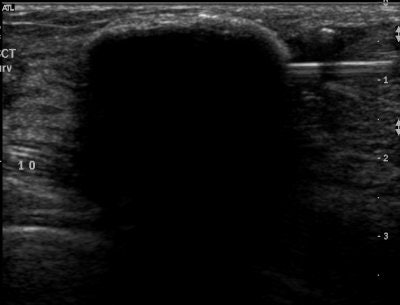

| Above, placement of cryoablation needle in the fibroadenoma. Middle, the ice ball forms at tip of cryoablation needle. Below, an illustration of ultrasound visualization of the ice ball. Images courtesy of Galil Medical. |

This method of destroying diseased tissue by applying cycles of freezing and thawing temperatures has been most commonly used for the treatment of renal tumors, prostate cancer, and endometriosis. For breast fibroadenoma, ultrasound is used to guide the cryoprobe, through which argon gas flows, and an ice ball forms at the tip engorging and then freezing the tumor.